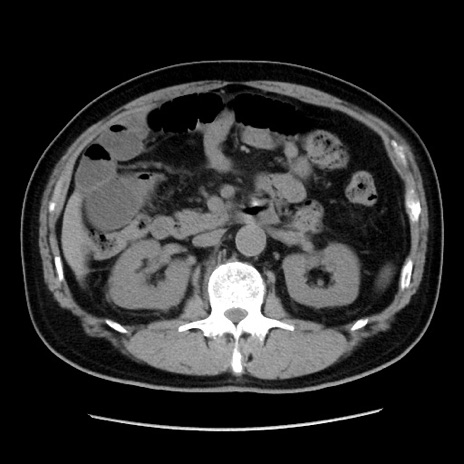

症例16(横断像)

【症例】 70歳代男性

【主訴】 腹痛、嘔吐

【現病歴】 約1ヶ月前より間欠的に腹痛と嘔吐あり、当院消化器内科を受診したところCTで多発する肝臓のLDAを指摘され、精査中であった。以降は消化器症状は安定していたが、2日前より嘔気と腹痛があり、同日より排便・排ガスが消失した。改善認めず、 本日、救急外来を受診した。

【既往歴】 大腸ポリープ切除後。

【身体所見】意識清明・会話良好、BT 36.3℃、BP 127/80mmHg、 P 80bpm、腹部:膨満あり、平坦・軟、上腹部正中および下腹部正中に圧痛あり、反跳痛なし、筋性防御なし。

【データ】WBC 7200、CRP 0.77